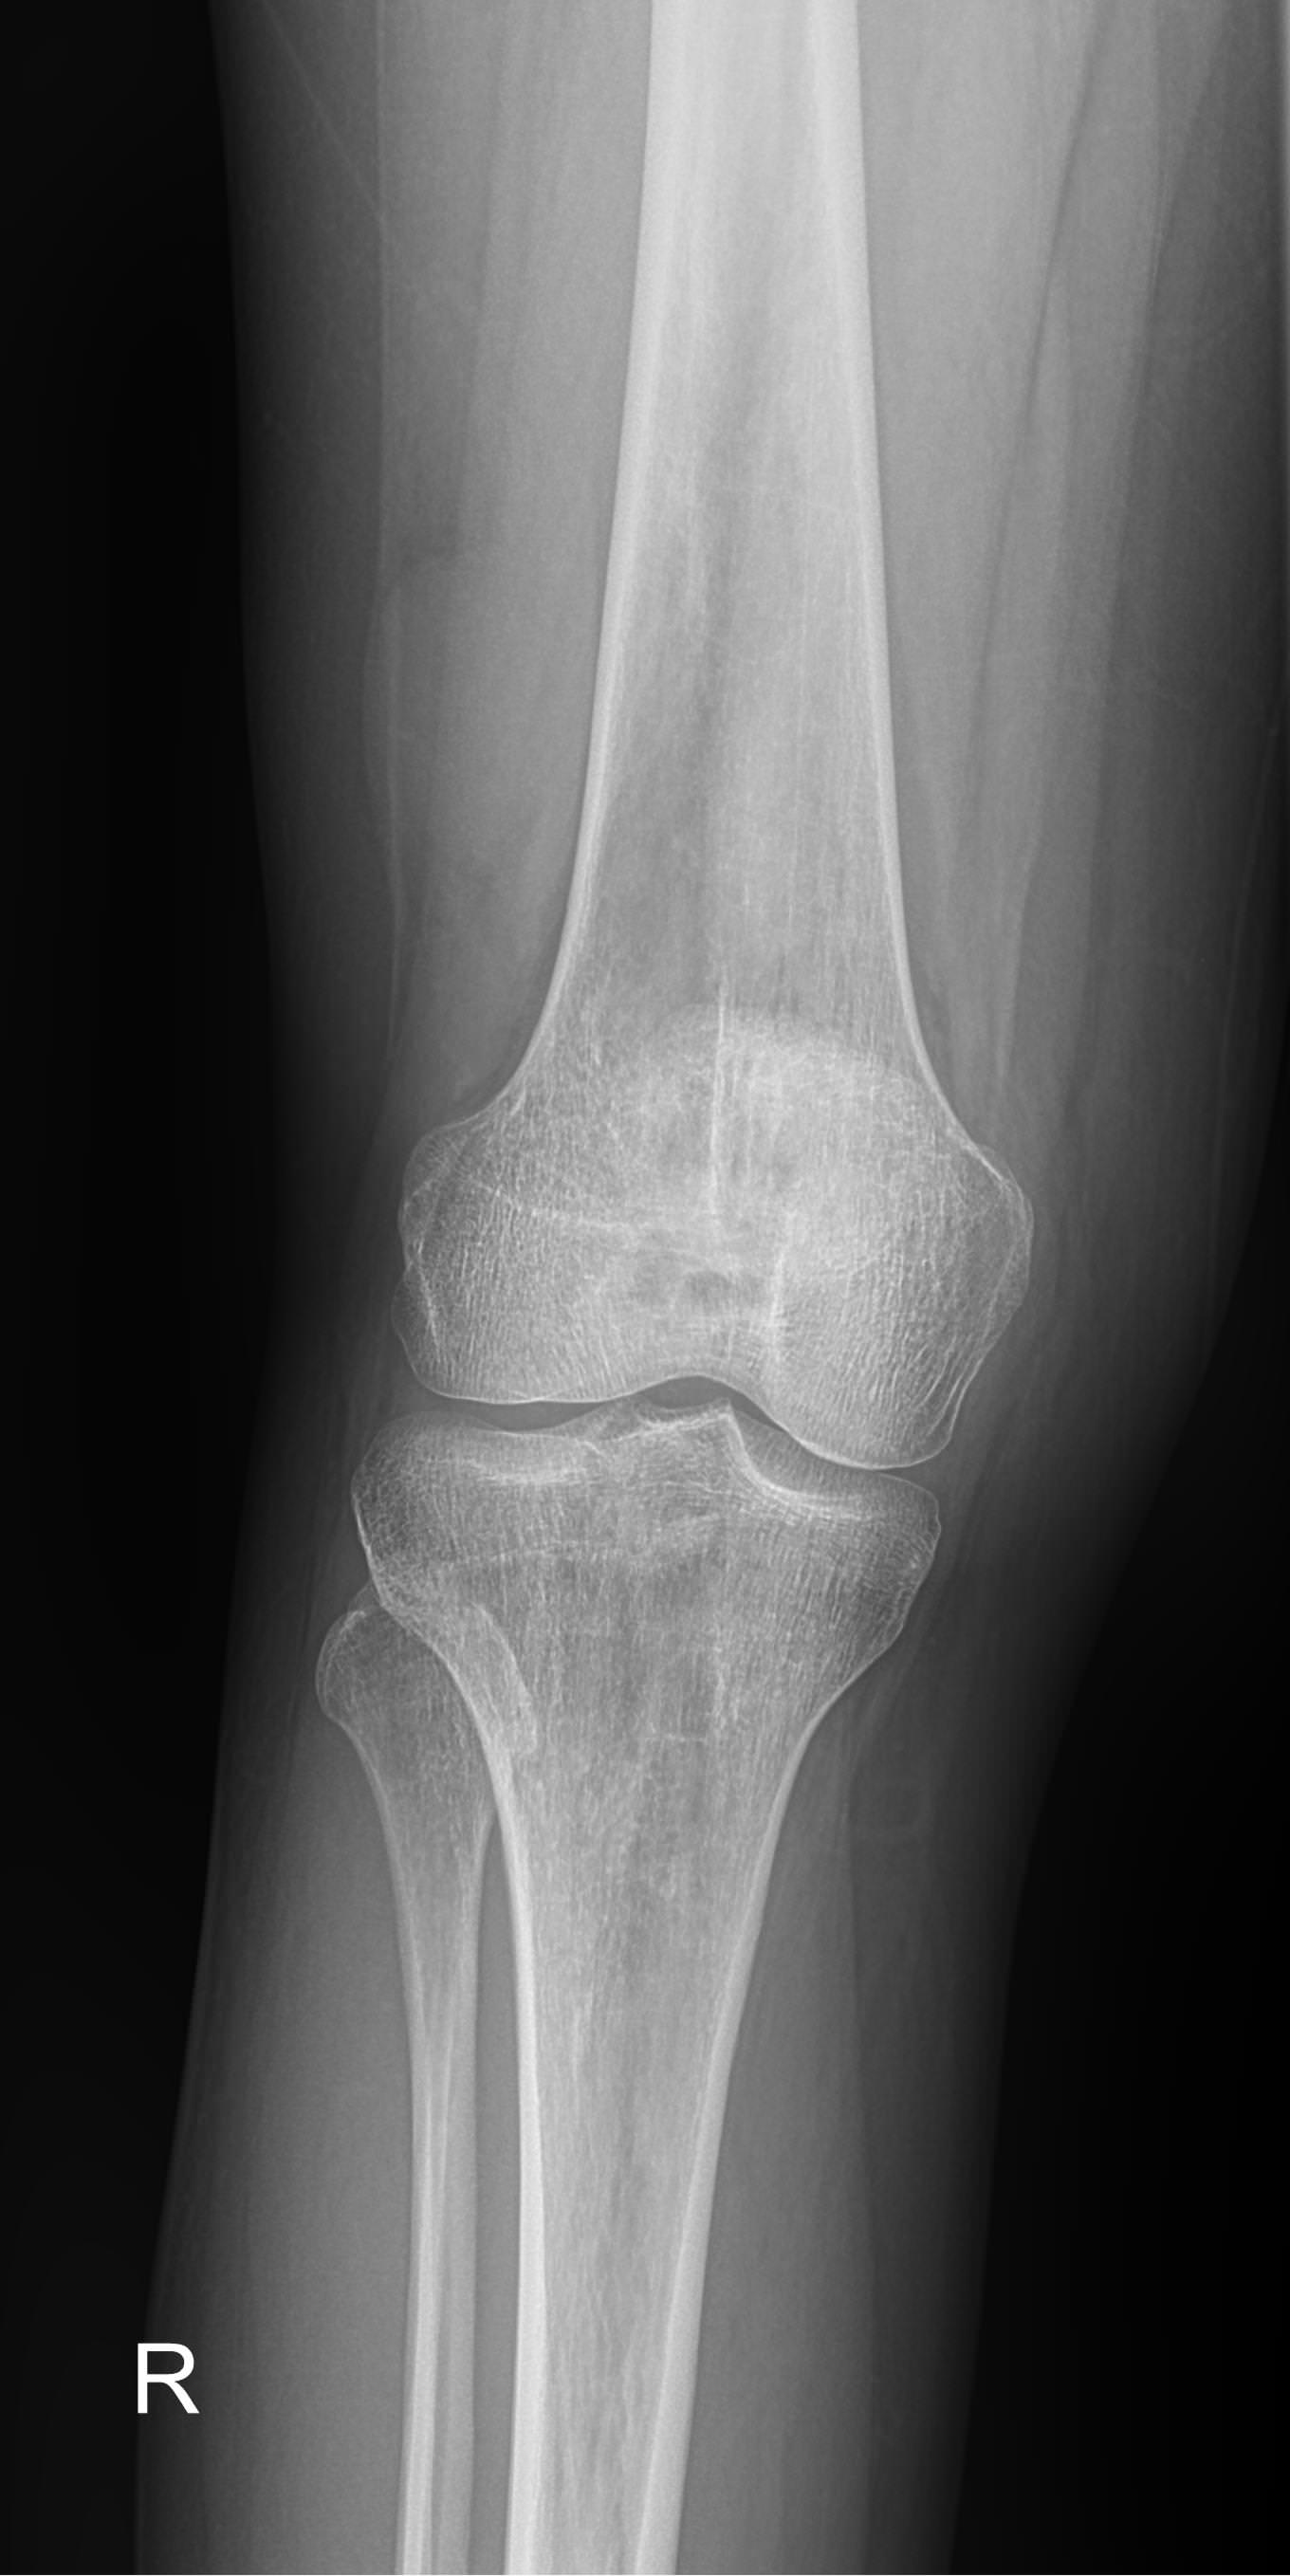

Рентген ― самый простой и быстрый метод диагностики поражения коленных суставов. Это неинвазивный и безболезненный , а также высокоинформативный способ увидеть внутреннее состояние колена. Современное рентгеновское оборудование использует минимально возможную дозу облучения. При этом на рентгенограмме отчетливо просматриваются части бедренной, малоберцовой и большеберцовой костей, надколенник, а также мягкие ткани вокруг них.

На рентгенограмме будут видны элементы сустава и патологические изменения в них:

• Суставная щель ― может быть расширена или сужена, причем неравномерно, иметь выпот, выросты, костные и хрящевые обломки;

• Соответствие друг другу суставных поверхностей ― естественное или вывих;

• Положение надколенника ― может быть неестественным;

• Состояние костной ткани: перелом, разрежение, уплотнение, размягчение, склерозирование;

• Мягкие ткани ― нормальные или отекшие, с инородными телами.